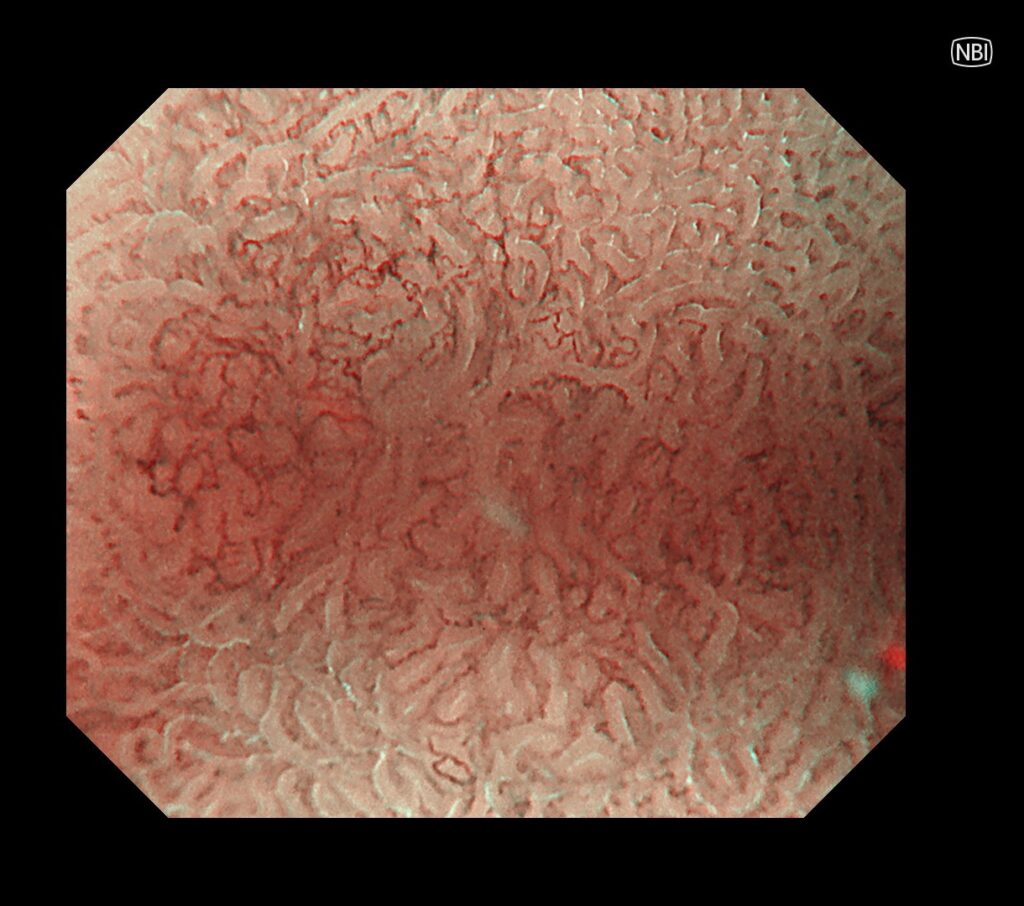

NBI拡大観察モード(倍率を上げて、癌の局在と範囲、組織型を確定させるモード)で、切除範囲をマーキングします。

マーキングから、病変摘出までわずか”3分”で終了。

胃癌のESDも入院せず、日帰りの時代が到来したと考えております。